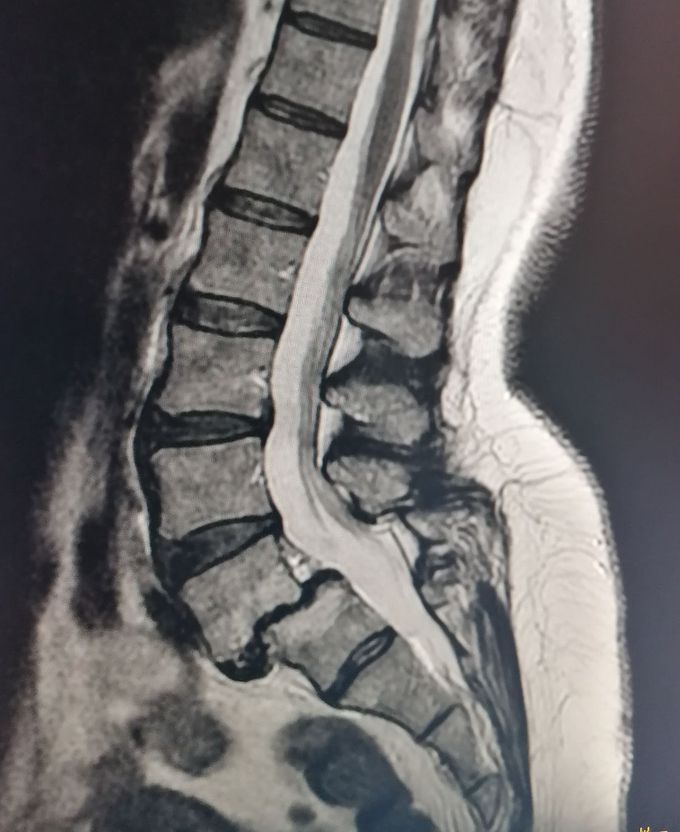

Anterolisthesis LV-SI

61 years old woman Lumbar spine MRI T2 sag